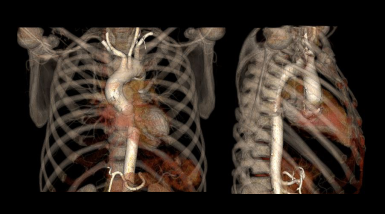

- Surface shaded images of aorta.